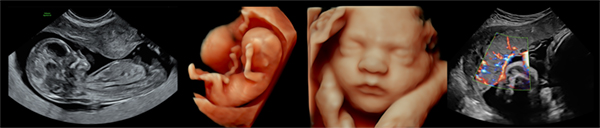

先進のハードウェアとフレキシブルなソフトウェアの融合により誕生したVoluson Unity Architectureが,短時間で迷いない診断をサポートします。

Voluson Signature 18は,AIを用いて開発された多くのクリニカルツールを搭載しました。自動化機能が,検査の一貫性と正確性を確保しつつ,反復動作を減らして日常業務の簡素化を目指します。

・表示モード Bモード,Mモード,カラードプラ,PW,3D/4D

・産科

・婦人科